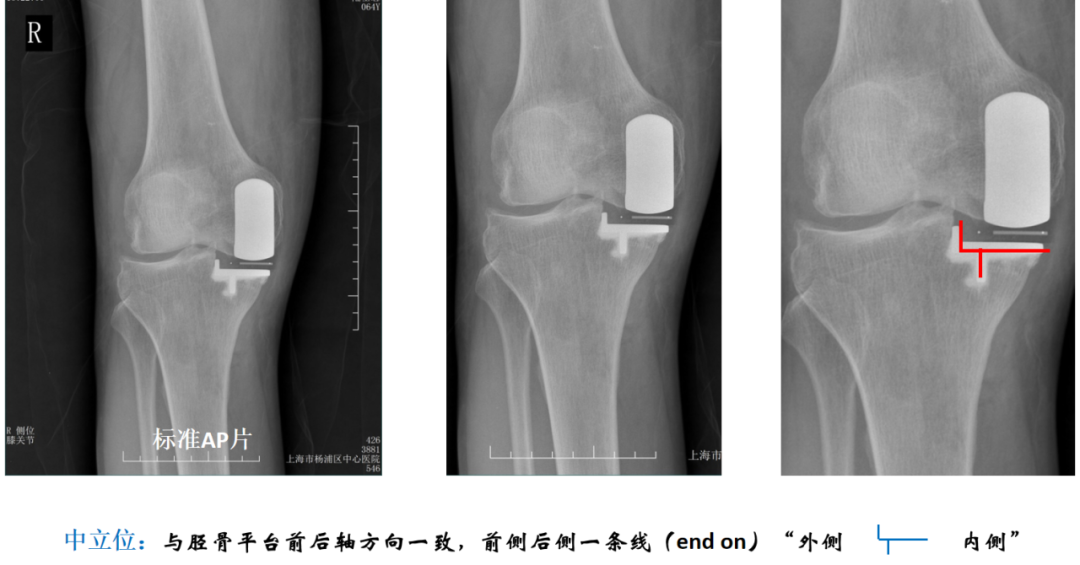

胫骨假体中立位(冠状面:无内外翻)

胫骨假体中立位:与胫骨AP位中轴线的垂线平行,水平截骨与胫骨轴线垂直。

胫骨假体中立位(横断面:无内外旋)